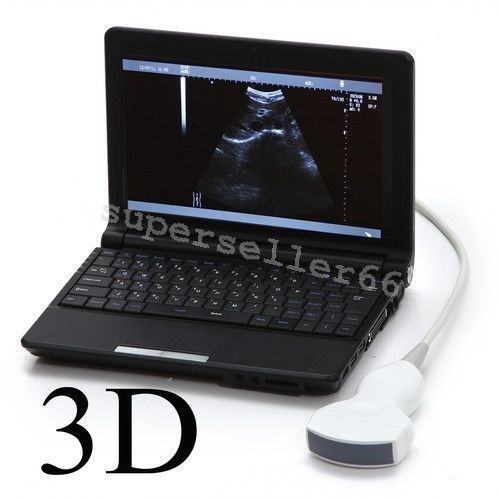

High-Resolution Display for Clear Imaging

The Ultrasound Scanner features a 10.1'' LCD screen that provides high-resolution images, ensuring that healthcare professionals can make accurate diagnoses. However, the clarity of ultrasound imaging is vital, because it directly impacts patient care. The intuitive interface makes it easy for users to navigate through various options, so they can focus on delivering quality healthcare.

Compact and Portable Design

The Ultrasound Scanner is designed with portability in mind, allowing easy transport between different locations. Healthcare providers need equipment that is both reliable and convenient, and this product meets those needs. Additionally, its lightweight design does not compromise functionality. So, This machine can be effortlessly moved, making it ideal for both in-office and mobile healthcare services.